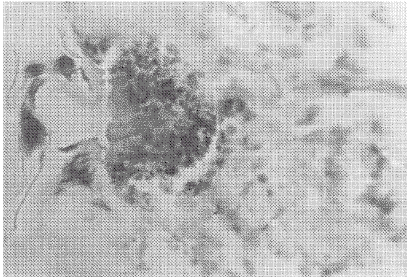

除空白对照组外(图版Ⅰ-1),所有感染兔均表现皮肤过敏和炎症反应(图版Ⅰ-2),蜱叮咬处皮肤表皮和真皮浅层交界处积聚大量嗜酸性粒细胞(图版Ⅱ-3),形成“cuff”结构,即在蜱的口器周围积聚多层嗜酸性粒细胞(图版Ⅱ-4),偶有数量不多的嗜碱性粒细胞出现,同时伴有单核细胞浸润,胞质脱落的细胞也较多。蜱叮咬处的表皮也出现皮肤反应,表现为细胞坏死及紧邻的细胞肿胀,有的出现空泡变性,胞核淡染。真皮浅层毛细血管内炎性细胞较多,有充血及出血现象。

3 感染长角血蜱幼虫部位嗜酸性粒细胞浸润(苏木素伊红染色,410×)

3 Exposed to Haemaphysalis longicornis larvae skin,eosinophil infiltration(Haematoidin-Eosin staining,410×)

4 感染长角血蜱幼虫部位嗜酸性粒细胞积聚,形成“cuff”结构(瑞氏染色,164×)

4 Exposed to Haemaphysalis longicornis larvae skin,eosinophil building up a “cuff”structure(Wright staining,164×)